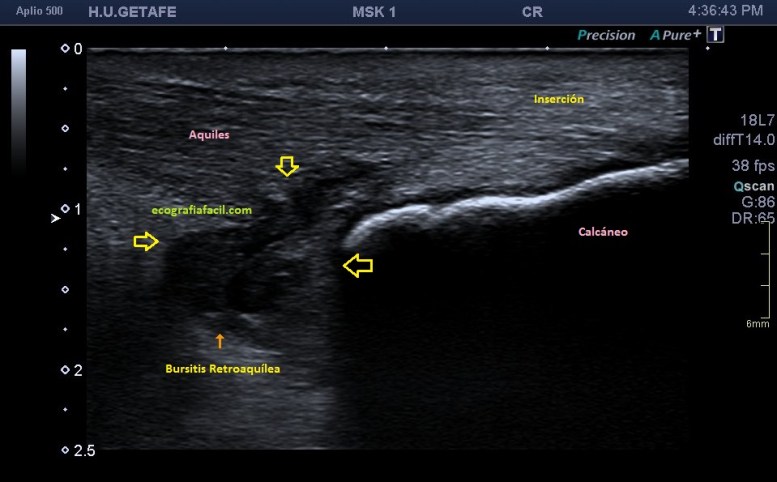

En el texto anterior hemos visto enmarañadamente muchos conceptos asociados a patologías que pueden darse en esta pequeña región del Aquiles. He nombrado el Síndrome de Haglund. Este es un síndrome que incluye tres aspectos, a nivel del aspecto posterior del calcáneo con una afectación de la bursa retroaquílea debido a la presencia de una exóstosis.

En muchas ocasiones vamos a encontrar calcificaciones de inserción o entensopatías, pero ver ecográficamente la afectación de la bursa es mucho menor. En muchas ocasiones, la radióloga necesita ampliaciones de estudio con radiología simple y con RMN para poder efectuar convenientemente este diagnóstico y nosotros, tenemos que ser muy minuciosos en la exploración ecográfica de esta región, conocer perfectamente ecoarquitectura normal de la región para poder identificar tanto los calcios insercionales como la bursitis retroaquílea, amén de la tendinopatía, ni que decir tiene a complicaciones tendinosas derivadas de estado avanzados de la patología como pudieran ser la roturas insercionales, parciales o totales.

Si observamos la bursitis retroaquílea de la imagen 11(flechas amarillas), además la exóstosis de la imagen 13 y deformidad en la piel, observable sin ecografía podemos estar ante un síndrome de Haglund de esos de libro…y tendremos una imagen ecográfica como la de la imagen 14.

Como has visto en la imagen 1, la bursa retroaquílea no debe verse, ese receso debe tener como mucho una mínima cantidad de líquido, que como digo es normal, pero no lo que observamos en la imagen 11 donde vemos una imagen heterogénea ocupando esa región.

En la imagen 14, como no podía ser de otra manera, observamos todo y es por definición la típica imagen de S.Haglund.